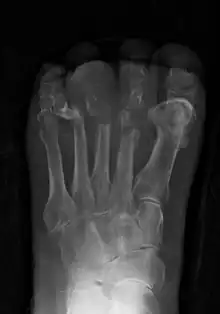

![]() | |

| Osteomyelitis of the 1st toe | |